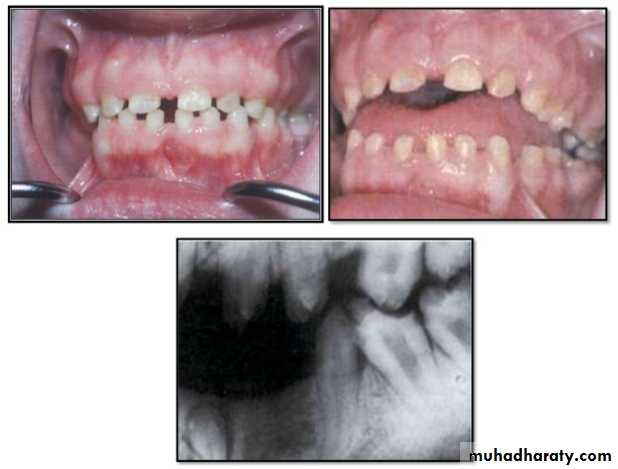

Hypodontia

Oligodontia

Anadontia

Developmental absence of all maxillary premolars and both mandibular second premolars. Note the retention of the maxillary primary canine as a result of the posterior position of the maxillary permanent canine.

CAUSES: may be the result of numerous independent pathologic mechanisms that can affect the orderly formation of the dental lamina (e.g.,orofaciodigital syndrome), failure of a tooth germ to develop at the optimal time, lack of necessary space imposed by a malformed jaw, and a genetically determined disproportion between tooth mass and jaw size.

MANAGEMENT: Missing teeth, abnormal occlusion, or altered facial appearance may cause patients psychologic

distress.

*Mild hypodontia by orthodontics.

*Severe cases by restorative,implant, and prosthetic procedures .